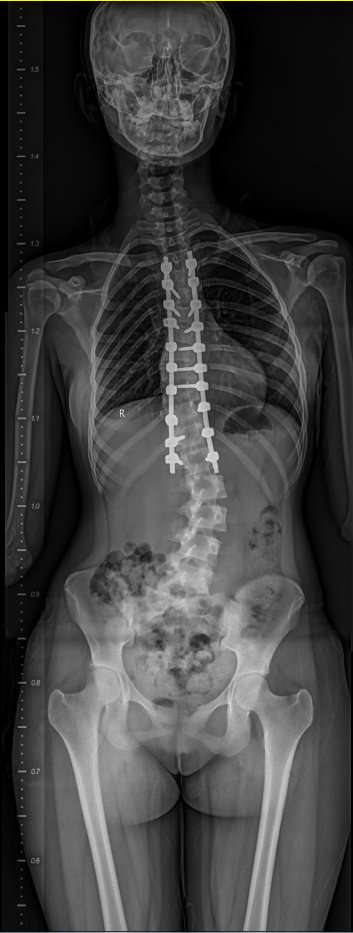

手术由脊柱与骨肿瘤病区副主任蔡璇教授主刀,李宇欢、王杰主治医师及刘璇规培医师协助,在全麻下实施后路多节段截骨矫形、植骨融合及内固定术。手术过程中需在大幅度矫正畸形的同时,严格防控脊髓神经损伤风险。神经电生理监测团队黄亚娟、孙丽君医师全程实时监测神经传导功能,为手术安全提供关键保障。在麻醉医师李路盼和手术室彭维、张宇坤主管护师的熟练配合下,历时6小时,手术顺利完成,术中出血量约600ml,未发生神经损伤等严重并发症。术后影像学评估显示,胸椎主弯矫形率超过90%,脊柱整体序列显著改善。术后,患者在多学科团队的协同管理下恢复良好,双下肢感觉及运动功能正常,身高增加7cm 以上。护理团队结合外籍患者需求,提供细致的围术期护理与康复指导,帮助患者顺利过渡至日常生活与学习状态。出院前,患者用英语向医护人员表达感谢:“Thank you for giving me a new life.”这不仅是对治疗效果的肯定,也体现了患者及家属对中国医疗技术与服务体系的高度认可。

图2 患者术后畸形改善明显